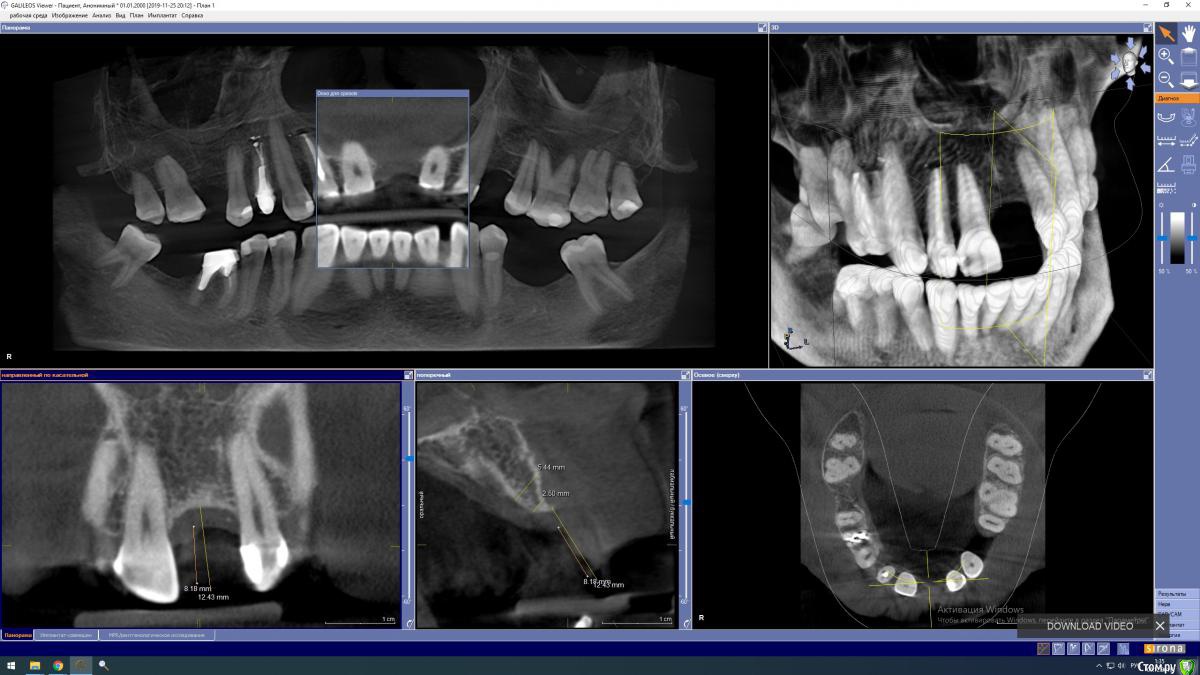

Estes Опубликовано 8 декабря, 2019 Поделиться Опубликовано 8 декабря, 2019 (изменено) Здравствуйте. Пришел знакомый на прием, провели КТ обследование, общий анамнез, диагностические модели. В анаменезе 2 года ранее- аугментация в области 21 , неудачно.Предложил пару вариантов:Вариант 1. верхняя челюсть - удалить 24 + консервация лунки + эндо 26, далее мостовидные протезы диоксид циркония 17-15-13, 12-11-22, 23-25-26, по необходимости - эндо указанных зубов, нижняя челюсть - коронка 46, мостовидный протез 34-37, вероятное эндо 37, возможно имплантация 47+коронка. Сроки проведения протезирования - 1-2 месяца, + срок на работу с имплантом 47- - 3-4 месяца. Второй вариант: Верхняя челюсть: костный блок 21+ мобилизация десны в области 11-22+Biooss+аутокость + 2 фиксирующих винта + мембрана Bioteck (3-4 пина)+ Аугментин 1000*2 7 дней+ Супрастин 1*2 4-6 дней . Проблемные зубы не удаляем, протезируем как есть мостовидным протезом 17-15, одиночная коронка 14. мостовидный протез 23-25. 26 зуб - предложено депульпировать, но пока пациент отказался, 46 - одиночная коронка.Через 6 месяцев - имплантация 21 + 3 месяца на остеинтеграцию + протезирование д/ц коронкой на инд. д/ц абатменте. Далее - составление нового плана по восстановлению 35,36 зубов и эндо 26. По ситуации - проблемные зубы удаляются при обострениях, и замещаются имплантами в отдаленные сроки. Пациент решительно настроен на второй план (по крайней мере, в части костной пластики 21, имплантации 21), о проблеме с гайморовой пазухой слева предупрежден, о рисках 14 в курсе. по 12 - я сам сомневаюсь - удалять - не удалять, реэндо делать или не делать - зуб с изменениями , но стабилен уже лет 10. Сейчас пока сделали жесткую каппу с 21 зубом, 24 зубом ,внешний вид ну в целом устраивает. Собирается посетить лор. Подскажите, вариант с костной пластикой - насколько целесообразен в области 21?По имплантационной системе: минимальный диаметр импланта МИС С1 - 3.3 мм, работаю только с МИС С1, первичная стабильность имплантов не высокая в целом. Кт пациента https://yadi.sk/d/y8USmowvcGCNkA :открывается RAR или монтируется на виртуальный диск при помощи UltaISO https://yadi.sk/d/x58WF-imVW3cag Изменено 8 декабря, 2019 пользователем Estes Ссылка на комментарий